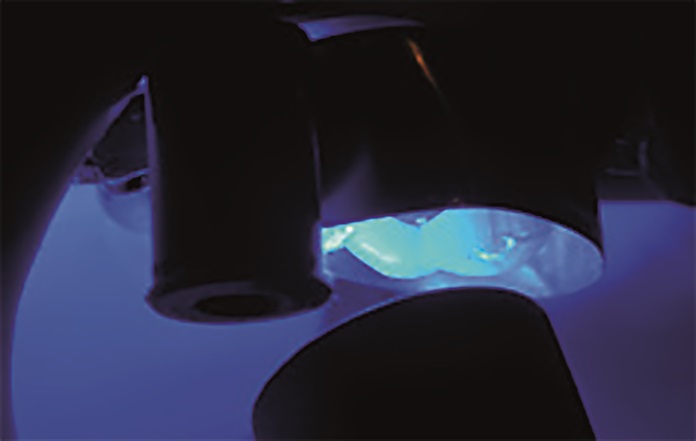

- Po osuszeniu OptiBond Universal został poddany polimeryzacji przez 10 sekund lampą polimeryzacyjną Demi™ Ultra (Kerr) (ryc. 7).

W przypadku odbudowy zęba 15 procedurę adhezyjną przeprowadzono z zastosowaniem protokołu wytrawiania self‑etch. Po dopasowaniu formówki Adapt SuperCap Matrix zaaplikowano OptiBond Universal zgodnie z wyżej opisanym protokołem — bez wcześniejszego zastosowania kwasu ortofosforowego (ryc. 12). Odstąpiono od użycia wkładów koronowo‑korzeniowych w tym przypadku. Wykonany dostęp endodontyczny umożliwił uzyskanie optymalnej retencji, a dzięki kształtowi zachowanych tkanek i długości korony zęba 15 osiągnięto rozległy efekt obręczy. Odbudowa została wykonana przy użyciu systemu SonicFill™2 – kompozytu bulk‑fill z końcówką dźwiękową do aktywacji materiału. SonicFill to kompozyt o wysokiej zawartości cząstek wypełniacza, zawierający opatentowaną żywicę ze specjalnymi modyfikatorami, reagującymi na energię dźwiękową. Na skutek aplikacji energii dźwiękowej i działania modyfikatora dochodzi do spadku lepkości i zwiększenia płynność materiału. Umożliwia to optymalne umieszczenie i dopasowanie wypełnienia do ścian ubytku. Po zaprzestaniu działania energii dźwiękowej kompozyt ponownie staje się bardziej lepki i zwarty, co sprzyja efektywnemu modelowaniu wypełnienia. Kompozyt ten cechuje się także optymalnym skurczem polimeryzacyjnym pozwalającym na wyższe stężenie inicjatorów sprzyjających bardziej efektywnemu procesowi polimeryzacji. Ponadto dzięki dopasowaniu współczynnika załamania światła i wydajnym mechanizmom utwardzania SonicFill2 jest możliwa jego polimeryzacja na maksymalnej głębokości wynoszącej 5mm. W związku z tym przed rozpoczęciem procedury zmierzono głębokość ubytku sondą, aby upewnić się, że grubość planowanej warstwy kompozytu będzie odpowiadała maksymalnej głębokości polimeryzacji tego materiału. Następnie wykonano odbudowę ubytku za pomocą jednej warstwy SonicFill2 (ryc. 13), który został spolimeryzowany za pomocą lampy Demi Ultra Light (ryc. 14). Po zakończeniu polimeryzacji usunięto formówkę, a wypełnienia w zębach 16 i 14 wykończono i wypolerowano za pomocą kolejnych krążków OptiDisc™ o coraz drobniejszym nasypie, a następnie jednoetapowego systemu Opti‑1Step™ (Kerr). Wygładzanie i polerowanie odgrywa istotną rolę w sposobie interakcji światła z uzupełnieniem. Mały, jednolity rozmiar cząsteczek materiału nanohybrydowego Harmonize™ został zaprojektowany w celu uzyskania optymalnej polerowalności.